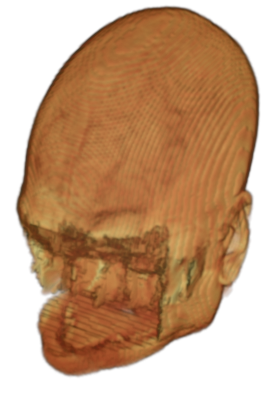

The digitalization of heath records has increased the risk of –and impact of– large scale data leaks. Although data compliance standards have been enacted to protect health records (HIPAA and GDPR), privacy of medical data is a growing concern. Three-dimensional scans such as magnetic resonance images (MRI) and computed tomography (CT), for example, contain an intrinsic privacy risk [Lotan et al.(2020)Lotan, Tschider, Sodickson, Caplan, Bruno, Zhang, and Lui]. Detailed renderings of the head can be crafted from 3D scans using techniques such as volumetric raycasting, as in Figure 1. This vulnerability can expose the patient’s identity if the renderings are matched to a face database [Mazura et al.(2012)Mazura, Juluru, Chen, Morgan, John, and Siegel, Lotan et al.(2020)Lotan, Tschider, Sodickson, Caplan, Bruno, Zhang, and Lui].

Therefore, in this work, we define a new class of de-identification techniques that remodels the privacy-sensitive regions without altering the content of medically relevant data (see Figure 1). Under such a remodeling approach, the face, eyes, oral and nasal cavities, etc. should exhibit realistic appearance and structure of appropriate size, but should otherwise be independent of the original data. To solve this task, we propose a novel model called Convex Privacy GAN, or CP-GAN, that conditions on a convex hull of the skull extracted from the scan to be de-identified. The generator learns to synthesize volumes that preserve medically-sensitive regions such as the brain, while non-invertibly remodeling privacy-sensitive characteristics from the original scan.